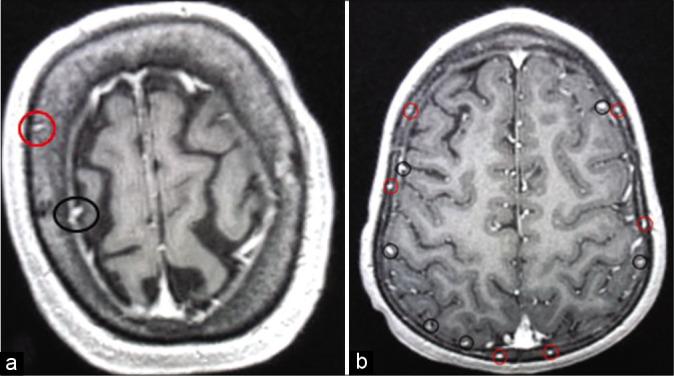

High-resolution, T1-weighted MRI scans from 20 adult and 16 pediatric subjects were selected for analysis. Skulls were divided into four regions, that is, frontal, parietal, temporal, and occipital. On each scan, a trained observer counted all diploic veins in every skull region. Each diploic vein was also followed to determine its final drainage pathway (i.e., dural venous sinus, dural vein, LL, or indeterminate).

In the adult age group, the frontal and occipital skull regions showed the highest number of diploic veins. However, the highest number of draining diploic veins connecting to the lacunae lateralis was found in the frontal and parietal skull region, just anterior and just posterior to the coronal suture. In the pediatric age group, the parietal skull region, just posterior to the coronal suture, showed the highest overall number of diploic veins and also the highest number of draining diploic veins connecting to the LL.

This study suggested that diploic venous density across the skull varies with age, with more parietal diploic veins in the pediatric age range, and more occipital and frontal diploic veins in adults. If the DVS is ultimately used for CSF diversion, our anatomical data point to optimal sites for the insertion of specially designed intraosseous infusion devices for the treatment of hydrocephalus. Likely the optimal sites for CSF diversion would be the parietal region just posterior to the coronal suture in children, and in adults, frontal and/or parietal just anterior or just posterior to the coronal suture.